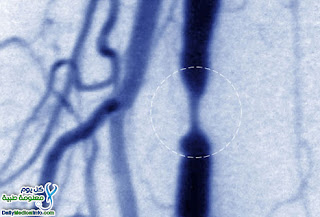

- الجراحه .. ضعف الانتصاب يأتي نتيجه ضيق الشرايين الواصله للقضيب .. ويكون ذلك غالبا في صغار السن لذلك يكون علاج هذا الانسداد جراحيا ..